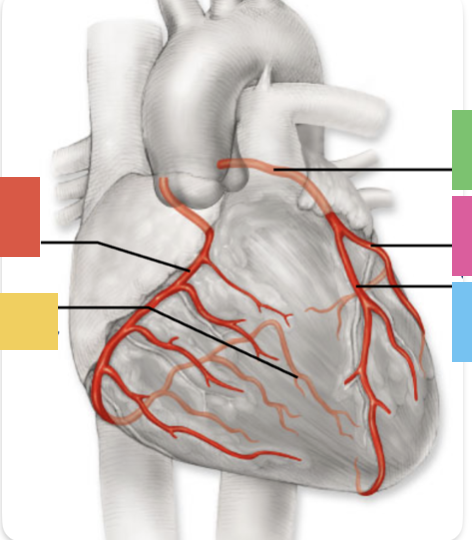

red

right coronary artery

yellow

posterior interventricular artery

green

left coronary artery

blue

anterior interventricular artery

pink

circumflex artery

coronary sinus